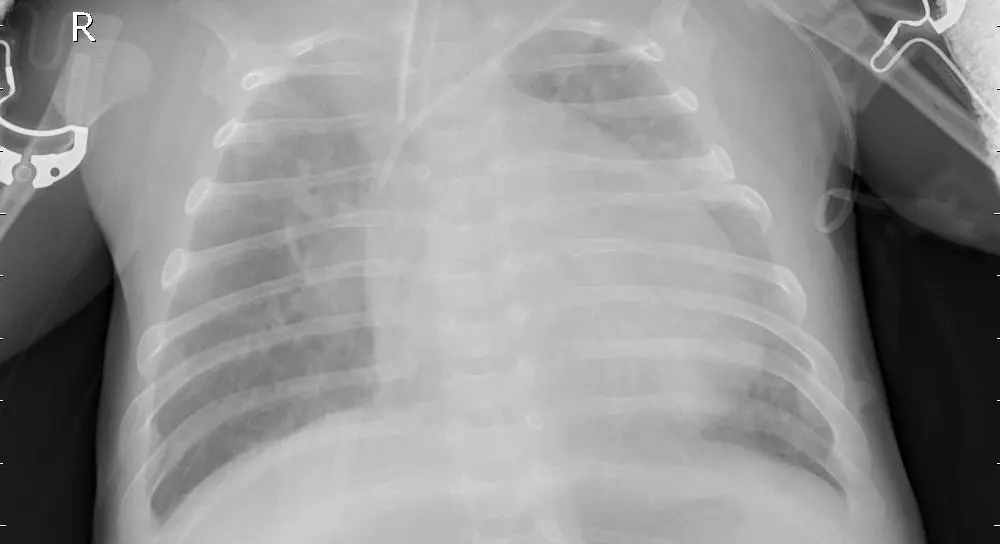

نموذج ذكاء اصطناعي باستخدام تقنيات Deep Learning لتحليل صور الأشعة الصدرية (Chest X-Ray) واكتشاف الإصابة بالالتهاب الرئوي (Pneumonia). المشروع يعتمد على شبكة CNN مدربة لتحليل الصور الطبية بدقة، مع توفير واجهة ويب بسيطة باستخدام Flask لرفع صورة الأشعة والحصول على النتيجة مباشرة. ما ستحصل عليه: * كود المشروع كامل بلغة Python * نموذج الذكاء الاصطناعي المدرب * تطبيق Flask لتحليل الصور * شرح طريقة تشغيل المشروع